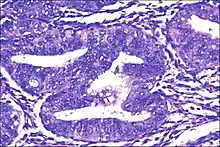

| Micrograph showing simple endometrial hyperplasia, where the gland-to-stroma ratio is preserved but the glands have an irregular shape and/or are dilated. Endometrial biopsy. H&E stain. | |

Endometrial hyperplasia is a condition of excessive proliferation of the cells of the endometrium, or inner lining of the uterus.

Like other hyperplastic disorders, endometrial hyperplasia initially represents a physiological response of endometrial tissue to the growth-promoting actions of estrogen. However, the gland-forming cells of a hyperplastic endometrium may also undergo changes over time which predispose them to cancerous transformation. Several histopathology subtypes of endometrial hyperplasia are recognisable to the pathologist, with different therapeutic and prognostic implications.[3]

- Endometrial hyperplasia (simple or complex) - Irregularity and cystic expansion of glands (simple) or crowding and budding of glands (complex) without worrisome changes in the appearance of individual gland cells. In one study, 1.6% of patients diagnosed with these abnormalities eventually developed endometrial cancer.[6]

- Atypical endometrial hyperplasia (simple or complex) - Simple or complex architectural changes, with worrisome (atypical) changes in gland cells, including cell stratification, tufting, loss of nuclear polarity, enlarged nuclei, and an increase in mitotic activity. These changes are similar to those seen in true cancer cells, but atypical hyperplasia does not show invasion into the connective tissues, the defining characteristic of cancer. The previously mentioned study found that 22% of patients with atypical hyperplasia eventually developed cancer.[6]